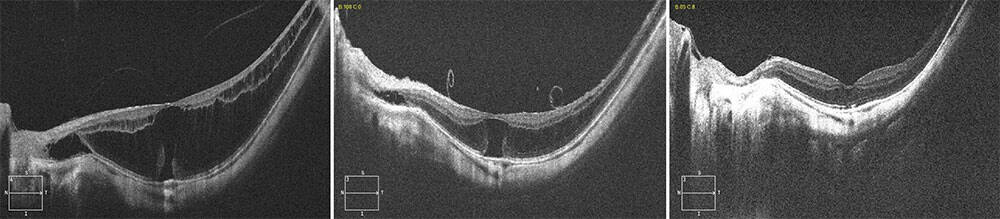

Figure 5. À gauche : Schisis du myope fort avec menace de trou maculaire. Au milieu : J7 postchirurgie avec Foveal Sparing. À droite : M10 postchirurgie.